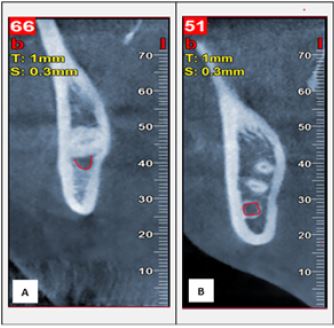

Among the 73 cone-beam computed tomography scans obtained, 113 lower third molars were found, of which 32 were male patients and 41 female patients. There were 49 third molars on the left side and 64 on the right side. A total of 61 (54 %) lower third molars were in direct contact with the IAC and 52 were not. Among the third molars in relation to the IAC, the lower location was more frequent in 45.9 % of the cases (p = 0.000) (Table 1) (Figures 4-5).

Proximity Relationship Between the Mandibular Third Molars and the IAC A: contact relationship. B: no contact

FIGURE 4

Elaborated by: the authors.